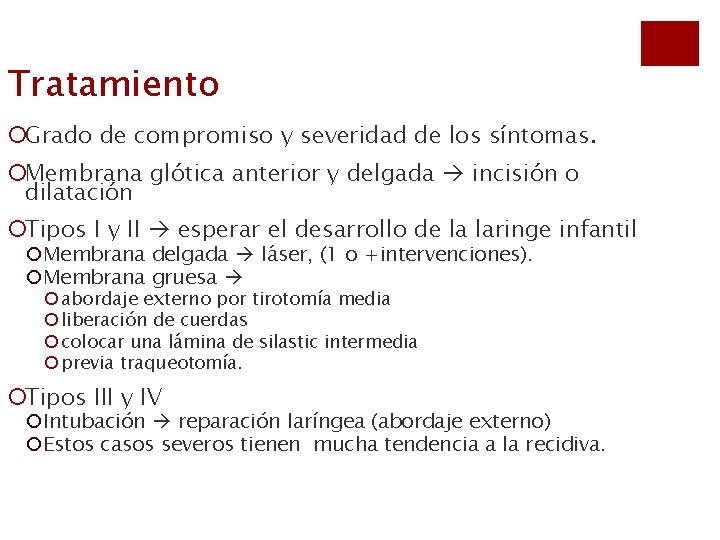

Tratamiento ¡Grado de compromiso y severidad de los síntomas. ¡Membrana glótica anterior y delgada incisión o dilatación ¡Tipos I y II esperar el desarrollo de la laringe infantil ¡Membrana delgada láser, (1 o +intervenciones). ¡Membrana gruesa ¡ abordaje externo por tirotomía media ¡ liberación de cuerdas ¡ colocar una lámina de silastic intermedia ¡ previa traqueotomía. ¡Tipos III y IV ¡Intubación reparación laríngea (abordaje externo) ¡Estos casos severos tienen mucha tendencia a la recidiva.